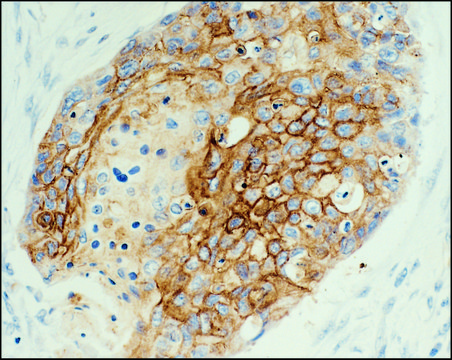

抗-表皮生长因子受体单克隆抗体 小鼠抗

E3138

抗-表皮生长因子受体单克隆抗体 小鼠抗,

clone F4, ascites fluid

E2760

clone 29.1, ascites fluid